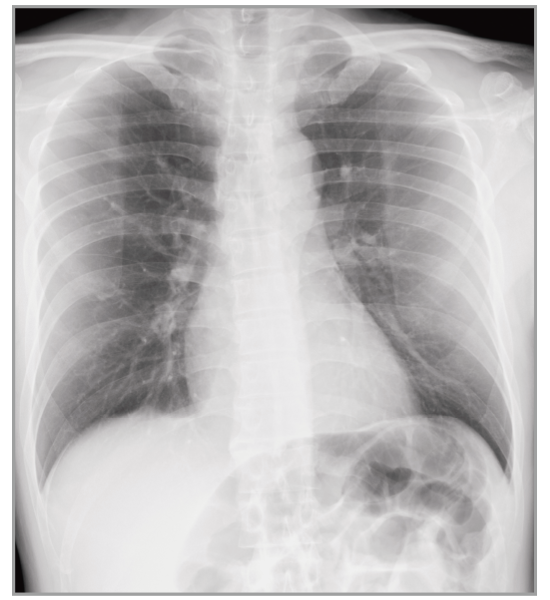

Dynamic Visualization II

Optimizes image quality using latest Exposure Data Recognizer

Advanced recognition algorithms using automatic  calculations of estimated 3D image data, identify the body part required and adjusts contrast, density and enhancement for optimised image display. (Option)

Comparison of Dynamic Visualization II vs. conventional processing images (Lumbar Spine)